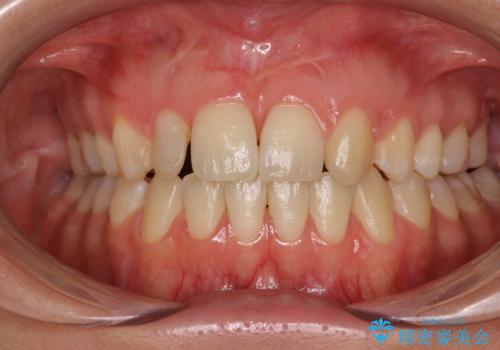

- 他院で矯正治療を終え、上顎前から2番目の歯の大きさを気にして来院された患者様です。

右側は小さく、左側は欠損により犬歯が前から2番に来ている状態でした。

矯正治療の段階で、矮小歯は前後にスペースが作ってあったため、極力左右対称の歯冠形態となるように補綴治療を行うこととしました。

歯根の太さや幅が左右で異なるため、歯肉ラインはどうしても左右非対称となってしまいますが、とても自然な口元となりました。